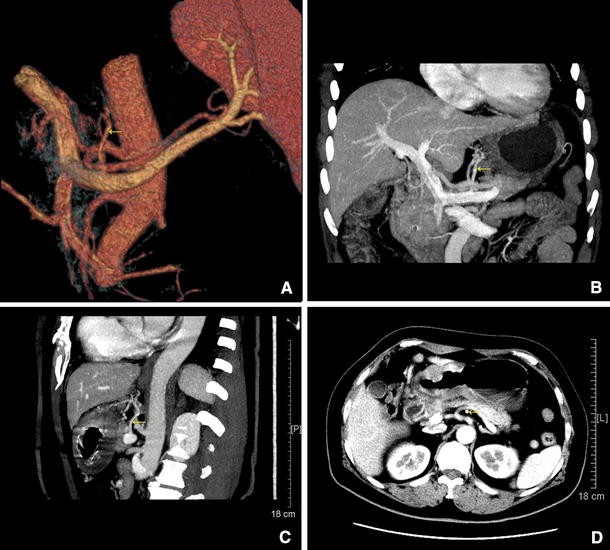

Using electronic caliper son three-dimensional CT reconstructions (Fig. 8), we measured the diameter and length of each LGV and the distances from its end to the splenoportal confluence and the root of the LGA were measured (Table 2). We found that the mean ± SD LGV diameter and length were 5.10 ± 0.40 and 37.40 ± 5.19 mm, respectively, and the mean ± SD distance from the end of the LGV to the splenoportal confluence was 13.05 ± 0.86 mm. The closer the LGV and LGA were to the root, the greater the distance between them; the mean ± SD distance from the end of the LGV to the root of the LGA was 13.85 ± 1.02 mm. Table 3 shows the mean LGV diameter and length and distances from its end to the splenoportal confluence and the root of the LGA in patients subdivided by age, sex, and BMI.

Fig. 8

figure 8

ad CT images showing the LGV running across the dorsal side of the splenic artery, and the portion pointed out by arrow refers to the LGV